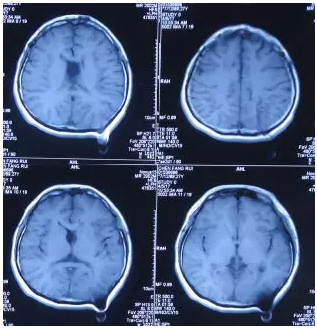

住院治疗第103天后即2012年8月20日,由搀扶下走路好转为独立起床、行走正常。脑脊液各项检查指标均正常后,住院治疗第106天后即2012年8月23日进行了脑室腹腔分流术,术后当天复查头颅CT:脑室分流管位置良好(图-11)。

图-11:2012年8月23日头CT

出院后2年余即2014年11月15日,通过微信传来在当地医院做的头部影像检查示未见异常(图-13),自述身体一切正常。

图-13:2014年11月15日头部影像

出院后4年零7个月即2017年4月5日,通过微信传来在当地医院做的头MRI检查示未见异常(图-14),自述工作和生活正常。

图-14:2017年4月5日头MRI(完)